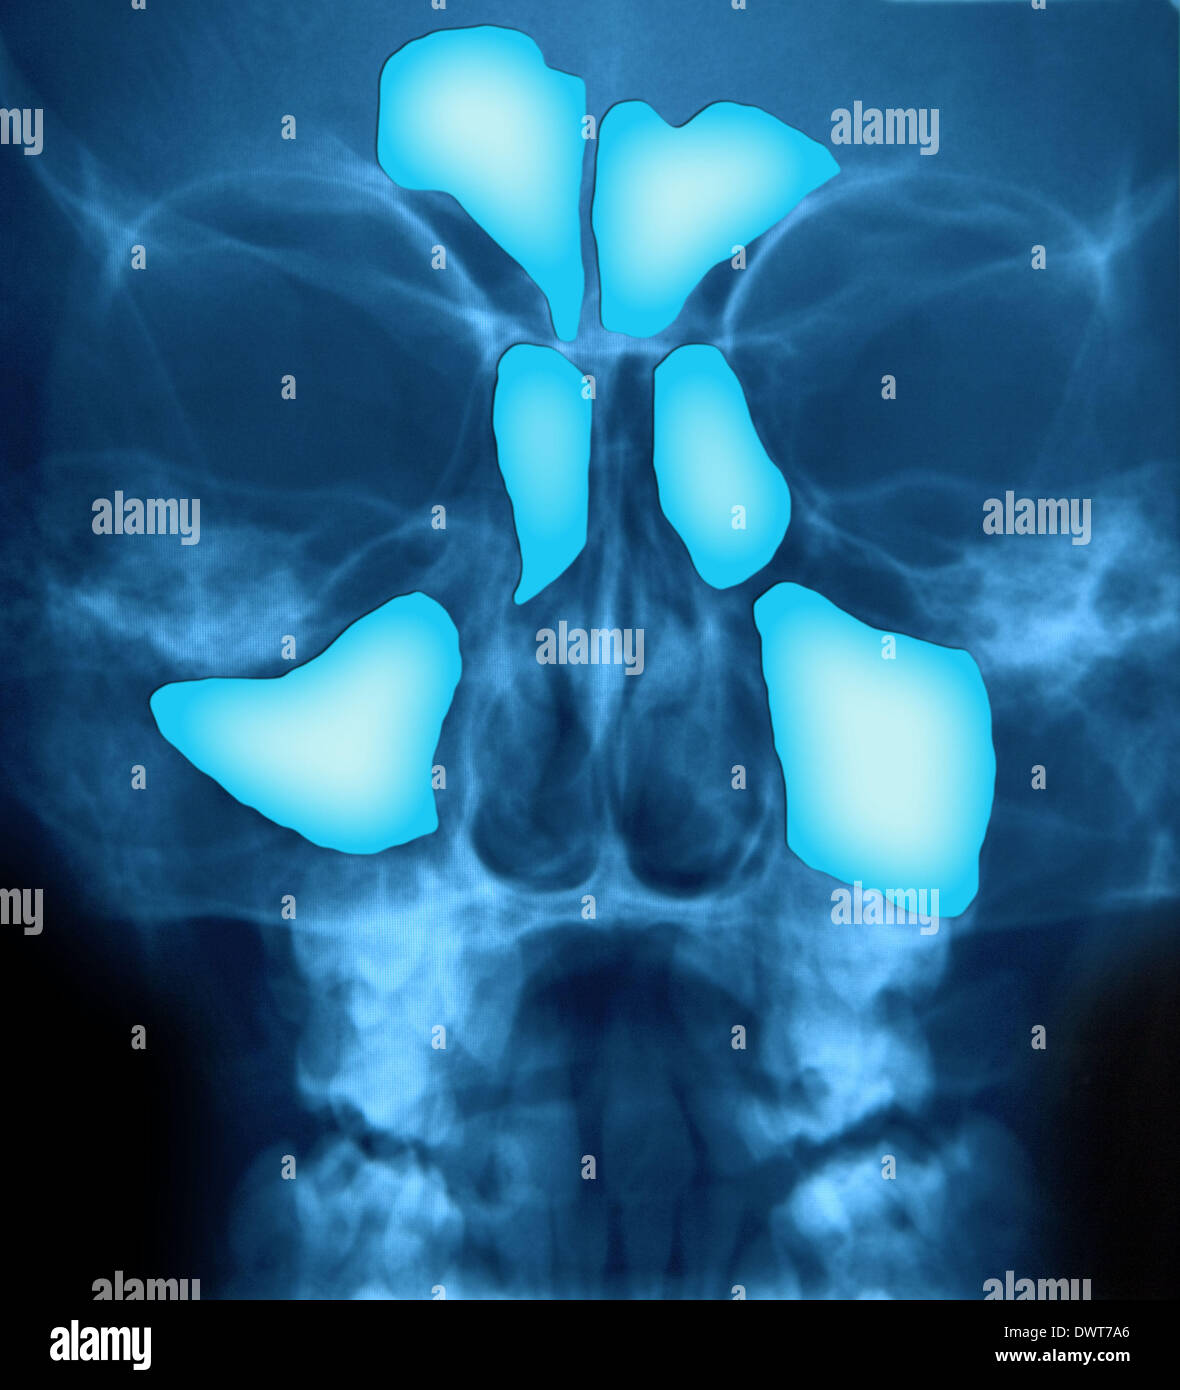

Sinusitis. Coloured Xray of the face of a patient with sinusitis, a Can An X Ray Show Sinus Infection When the sinus openings become blocked or too much mucus builds up, bacteria and other germs can grow. A computerized tomography (ct) scan gives a more thorough view of the sinuses, and it is usually preferred. This can lead to an infection and. Perform an anterior rhinoscopy (using an otoscope or a nasal speculum and headlight) to identify: Inflammation and. Can An X Ray Show Sinus Infection.